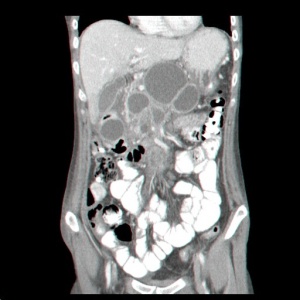

- טומוגרפיה ממוחשבת – נראה באיזור הלבלב גוש או גושים בד"כ בעלי גבולות ברורים המכילים בתוכם נוזל (תצלום 3.9).

| תצלום 3.9: כיסיות מדומות מרובות (חץ) באיזור הלבלב בשני חתכי CT. | |